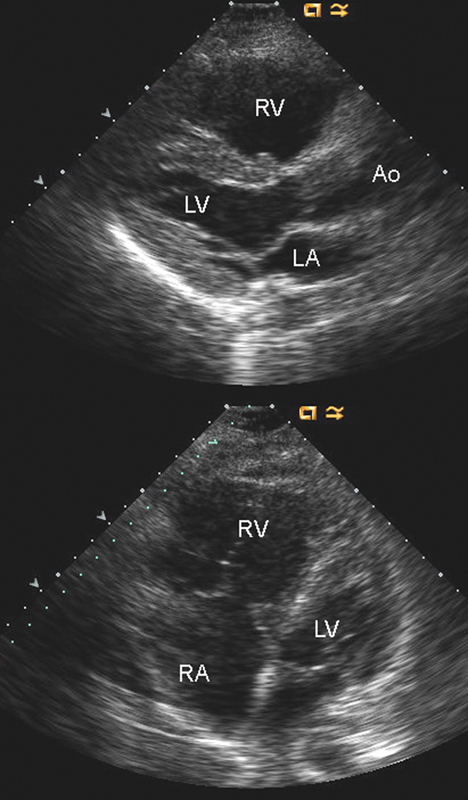

فحوصات تشخيصية لبعض امراض القلب والشرايين التاجية